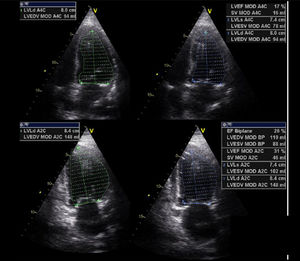

Valoración del volumen sistólico (fig. 2)Se puede realizar por medio de la integral velocidad-tiempo (IVT) y el diámetro del tracto de salida del ventrículo izquierdo (TSVI).

Estimación del volumen sistólico (VS) y del gasto cardiaco (CO) a través de la integral de velocidad (VTI) y radio (r) del tracto de salida del ventrículo izquierdo (TSVI). A) Paraesternal izquierdo ventrículo izquierdo en sístole. B) Zoom TSVI. C) Doppler pulsado TSVI 5C apical. D) Cálculos.

Un IVTTSVI<11cm se correlaciona con un índice cardiaco <2 l/min17,18.